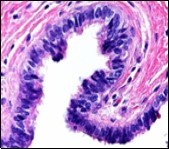

Alternatively, cutaneous ciliated cyst can be lined by non ciliated cuboidal or columnar epithelium with intermingled intercalated, dark or round peg cells. Foci of squamous metaplasia can be occasionally exemplified in the adherent epithelium whereas mucinous cells or apocrine-like features are exceptional 6, 8. Figure 1, Figure 2, Figure 3, Figure 4, Figure 5, Figure 6, Figure 7, Figure 8, Figure 9, Figure 10, Figure 11, Figure 12. 11, 12, 13, 14, 15, 16, 17, 18, 19.

Figure 1.Ciliated cutaneous cyst lined by pseudostratified ciliated columnar epithelium and a supporting fibro-connective tissue stroma 11.